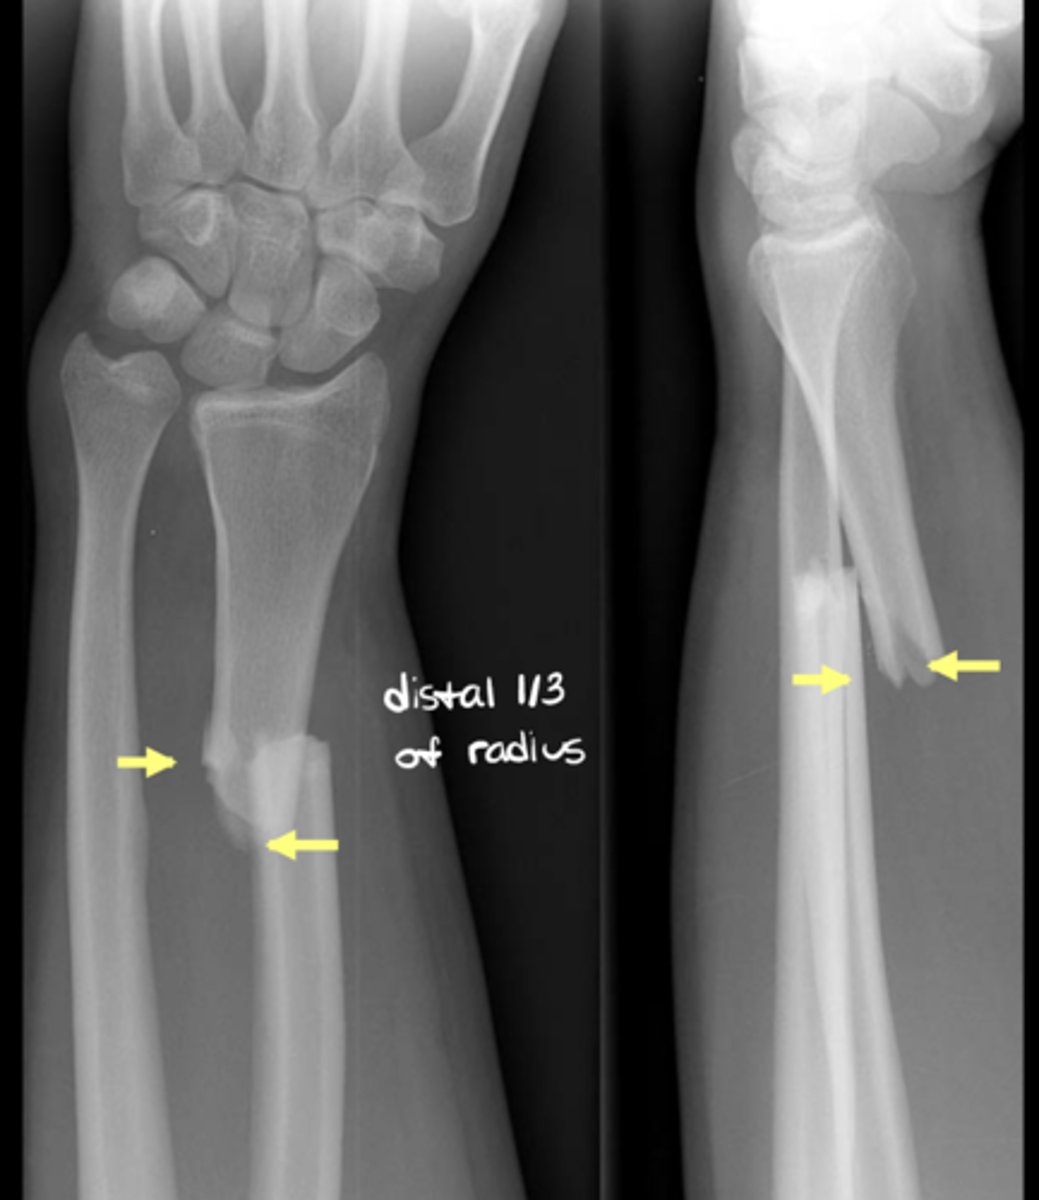

What is the position of fragments (under #3 "relationship of fragments")? What is an abnormality known as?

Degree of apposition at osseous ends; abnormality = displacement

What is the alignment of fragments (under #3 "relationship of fragments)? What is an abnormality known as?

Angular relationship; one fragment to another; abnormality = deviation

What does good position, good alignment look like vs. displaced with deviated alignment?

See image.

Name displacement based on the ________ fracture end in anatomical position

DISTAL!! -- i.e., "displaced medial, posterior, and overriding"

Name deviation based on the ________ bone angle in the ________ direction

DISTAL!! -- i.e., "deviated medial and anterior"